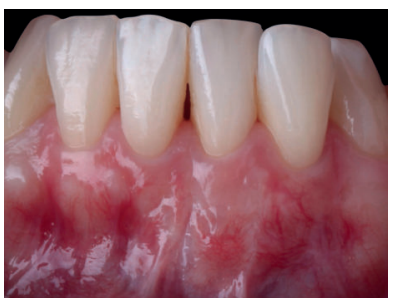

Mujer de 23 años que acudió a nuestra consulta debido a la presencia de múltiples recesiones gingivales desde el diente 32 al 42. La paciente refiere que nota sus dientes más largos, no presenta problemas de hipersensibilidad y había terminado el tratamiento ortodóncico hacía 1 año. La historia médica de la paciente no mostraba datos relevantes. No informó de alergias y no tomaba medicación de ningún tipo. El examen clínico periodontal reveló múltiples recesiones gingivales vestibulares que afectaban a los dientes 32, 31, 41 y 42 (Figura 9), con ausencia de tejido queratinizado apical a las recesiones de los dientes 31 y 32. Tras el estudio radiográfico (Figura 10) se observa pérdida ósea horizontal leve entre los incisivos inferiores (clase III de Miller y RT2 de Cairo).

Previamente a la intervención, la paciente se enjuagó durante un minuto con un colutorio de clorhexidina. La técnica quirúrgica comenzó con la preparación del lecho receptor, se realizaron incisiones intrasulculares a nivel cervical hasta la línea ángulo de todos los dientes del frente antero-inferior (33-43), desinsertando la base de la papila sin seccionarla con la ayuda de instrumentos de tunelización. Posteriormente se realizó una incisión en el fondo de vestíbulo (Figura 11). A continuación, se obtuvo un injerto de tejido conectivo del paladar introduciéndolo en el lecho receptor, siendo todas las suturas realizadas de la misma manera que en el caso clínico 1, usando tanto material reabsorbible como no reabsorbible de 5/0 y 6/0 ceros (Figura 12).

El control a la semana (Figura 13) presentaba inflamación moderada y a las 2 semanas (Figura 14) se retiraron los puntos de sutura. La paciente acudió a los 4 meses (Figura 15) y al año (Figura 16) a visitas de revisión, donde se apreció una buena banda de tejido queratinizado y una pequeña cicatriz.